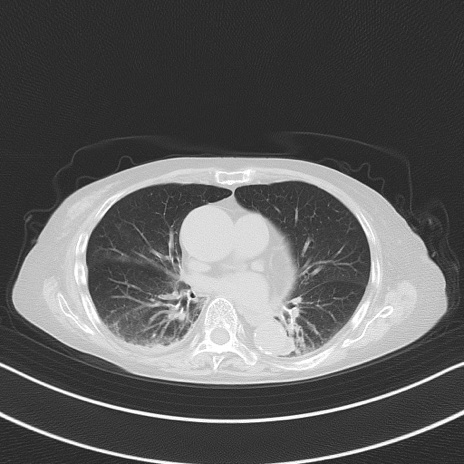

他院CT